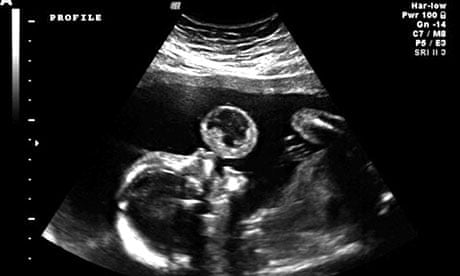

Tammy Gonazalez z Miami na Florydzie robiła rutynowe badanie USG. Nagle zauważyła, że jej dziecko zdaje się wydmuchiwać z ust olbrzymią bańkę.

Po dokładnym zbadaniu płodu, lekarze orzekli coś strasznego. „Bańka” okazała się być potworniakiem, czyli bardzo rzadkim nowotworem.

Dziecko nie wydmuchiwało bańki z ust. Zamiast tego, w tym miejscu rozwijał się nowotwór.

Potworniak okazał się zbyt duży, aby można było go usunąć. Lekarze postanowili więc odciąć go i pozostawić w worku owodniowym, aż do narodzin dziecka.

Gdy podczas narodzin dziecka wyciągnięto guza, okazał się być mniejszy niż pierwotnie zakładano.